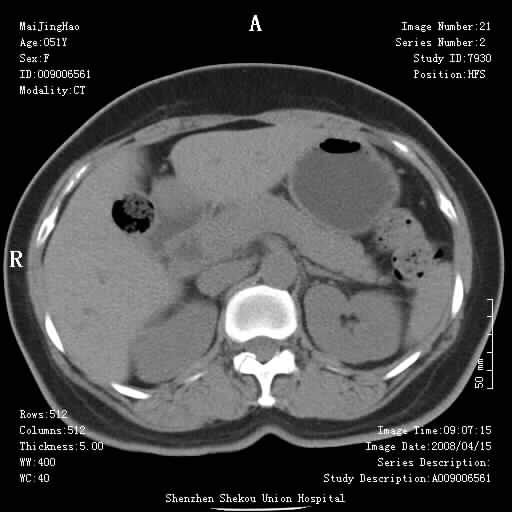

以下是引用liangshusheng在2008-4-26 12:34:00的发言:[br]11年前做的手术现在还有积气,可能吗?还是考虑有胆管炎产气,胰头部增大,建议做增强

以下是引用听蝉观竹在2008-4-27 10:10:00的发言:[br]关于胰头大小问题有几种测量方法和正常值:[br][br]1、直量法:横径<4cm;[br]2、胰头横径与相邻层面椎体横径的比值为二分之一,超过椎体横径就提示胰头增大;[br]3、正常组成年人肠系膜上动、静脉水平夹角正常值范围为4.9°~34.7°大于35°提示胰头增大。[br][br]上述方法只是一种具体的判断,是“量”的评估,更重要的是“质”的评估:一是观察边缘是否光滑,有无局部隆起,有无分叶;二是观察密度(增强,尤其在动脉期和门脉期)是否均匀。[br][br]所以对于胰头是否有异常不仅仅是是目测可以解决问题的,不要轻易就说“胰头增大”。还有一个问题就是测量胰头应该在增强ct上进行,这样可以避免将血管测量进去。[br][br]为什么啰嗦讲怎么多,因为我们实际工作中同样存在影像科医生和临床医生动不动就说胰头增大,说是胰头癌。大家看看是不是这种情况?[br][br] 我个人观点-----本病例的胰头不增大。[br][br][本贴已被 听蝉观竹 于 2008-4-27 10:12:41 修改过]